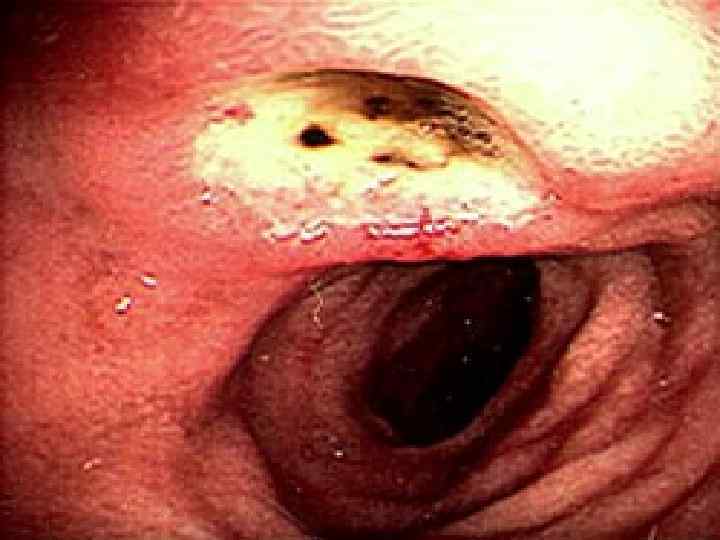

Перфорация язвы желудка и ДПК Анамнез Наличие язвы в анамнезе — у 80 90% больных; «немые» язвы — у 10 15% больных; наличие продромальных симптомов (боль, тошнота, рвота). Характерно острое начало с боли в животе, напряжение мышц брюшной стенки. Начальная реакция организма на перфорацию язвы схожа с патогенезом шока, что связано с ожогом брюшины кислым желудочным соком, излившимся в брюшную полость. В последующем развивается серозно фибринозный, а затем гнойный перитонит.

Клиническая картина Характерна резкая боль в эпигастральной области. Сначала локализуется в верхних отделах живота, при прободении язвы 12 перстной кишки – больше справа от срединной линии, затем по всей правой половине живота, захватывая правую подвздошную область, и далее – по всему животу. Возможна иррадиация болей в плечи и правую лопатку. Может быть рвота «кофейной гущей» или, редко, ярко алой кровью. Характерно исчезновение печеночной тупости из за наличия свободного газа в брюшной полости.

Клиническая картина Основные симптомы: Симптом Спижарного — исчезновение печеночной тупости при перкуссии; Симптом Де Кервена пальцевидное втяжение рентгеновской тени желудка по большой кривизне, обусловленное рефлекторным спазмом циркулярных мышц желудка при язве малой кривизны.

Клиническая картина Основные симптомы: Симптом Щеткина Блюмберга — усиление боли при резком снятии пальпирующей руки от брюшной стенки; Симптом Воскресенского (симптом «рубашки» ) — ощущение усиления боли в правой подвздошной области при быстром проведении правой ладонью по передней брюшной стенке правого подреберья вниз по натянутой левой рукой хирурга рубашке больного.